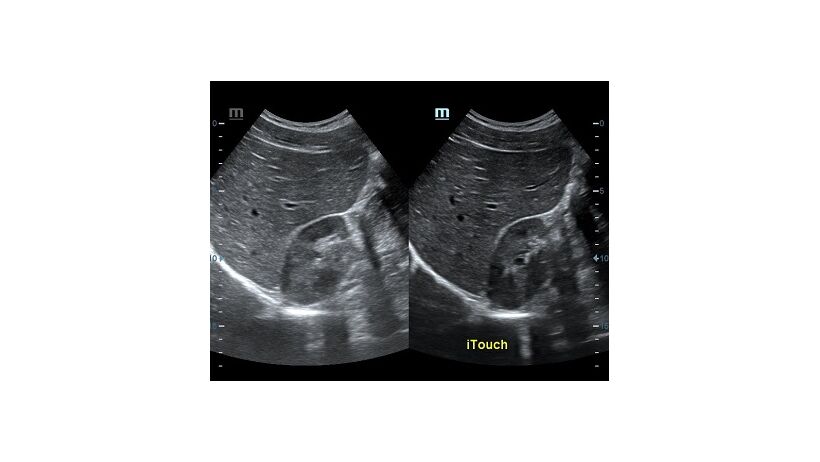

Оптимизация изображения происходит и за счет постобработки. Наиболее часто используемый инструмент - общее усиление (Gain). Усиление делает изображение «ярче», но чем сильнее усиление, тем меньше различия между структурами. Также используются усиление по времени (TGC) и усиление по длине (LGC), которые позволяют изменять отображение на экране послойно, позволяя подсветить гипоэхогенные участки, или, наоборот, снизить визуально эхогенность слишком ярких моментов. Данный вид оптимизации требует много времени, для упрощения работы доктора на приборах Mindray внедрена система автоматической оптимизации - iTouch.